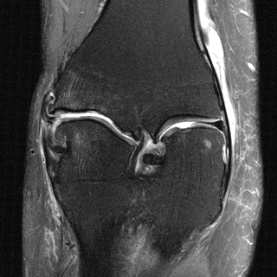

Deep Learning (DL) methods have shown promising results for solving ill-posed inverse problems such as MR image reconstruction from undersampled $k$-space data. However, these approaches currently have no guarantees for reconstruction quality and the reliability of such algorithms is only poorly understood. Adversarial attacks offer a valuable tool to understand possible failure modes and worst case performance of DL-based reconstruction algorithms. In this paper we describe adversarial attacks on multi-coil $k$-space measurements and evaluate them on the recently proposed E2E-VarNet and a simpler UNet-based model. In contrast to prior work, the attacks are targeted to specifically alter diagnostically relevant regions. Using two realistic attack models (adversarial $k$-space noise and adversarial rotations) we are able to show that current state-of-the-art DL-based reconstruction algorithms are indeed sensitive to such perturbations to a degree where relevant diagnostic information may be lost. Surprisingly, in our experiments the UNet and the more sophisticated E2E-VarNet were similarly sensitive to such attacks. Our findings add further to the evidence that caution must be exercised as DL-based methods move closer to clinical practice.